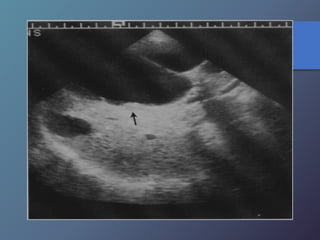

Síndrome de Budd-chiari

• Se caracteriza por la oclusión de las venas hepáticas.

• Esta relacionado con anomalías en la coagulación (policitemia

vera, leucemia crónica, traumatismos, carcinoma renal, chc

primario, embarazo).

• Clínica: Ascitis, dolor en hipocondrio derecho, hepatomegalia y

esplenomegalia.

• Ecográficamente: presencia de liquido (ascitis), aumento en los

diámetros hepáticos y esplénicos, infarto hemorrágico

hepático, aumento de la ecogenicidad en las aéreas infartadas.

• Al Doppler se aprecia aumento del flujo a nivel del lóbulo

caudado e hipertrofia del mismo, incapacidad para visualizar

las venas hepáticas.

Síndrome de Budd-chiari •Se caracteriza por la oclusión de las venas hepáticas. • Esta relacionado con anomalías en la coagulación (policitemia vera, leucemia crónica, traumatismos, carcinoma renal, chc primario, embarazo). • Clínica: Ascitis, dolor en hipocondrio derecho, hepatomegalia y esplenomegalia. • Ecográficamente: presencia de liquido (ascitis), aumento en los diámetros hepáticos y esplénicos, infarto hemorrágico hepático, aumento de la ecogenicidad en las aéreas infartadas. • Al Doppler se aprecia aumento del flujo a nivel del lóbulo caudado e hipertrofia del mismo, incapacidad para visualizar las venas hepáticas.